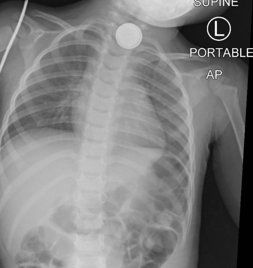

Caregivers should be educated to give children ≥12 months old two teaspoons of honey every 10 minutes while en route to the Emergency Room. Also, these children should never be forced to vomit. Other than honey, they should be kept NPO. These batteries on plain film have the characteristic halo sign or double ring appearance. Removal protocol is based on age and size of the battery ingested. For all patients <12 years old with a battery radiographically seen in the esophagus, removal needs to occur immediately.